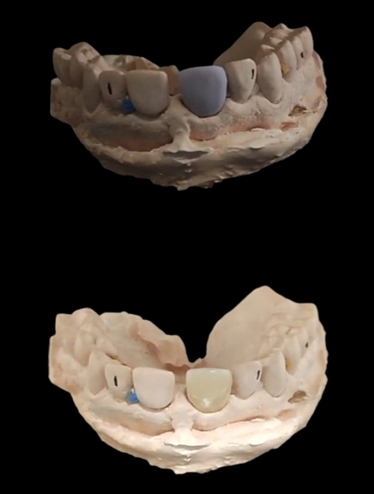

Tecnología CAD/CAM

Nuestro laboratorio cuenta con la tecnología CAD/CAM más avanzada, que nos permite diseñar y fabricar prótesis dentales personalizadas con precisión y velocidad.

– Diseño y fabricación de prótesis dentales (coronas, carillas, puentes, coronas sobre implantes , incrustaciones y impresión de modelos de trabajo en 3D.

Trabajamos en materiales como el zirconio, Disilicato de litio, PMMA y Ceromero)

Carillas de Disilicato de Litio

Coronas de Disilicato